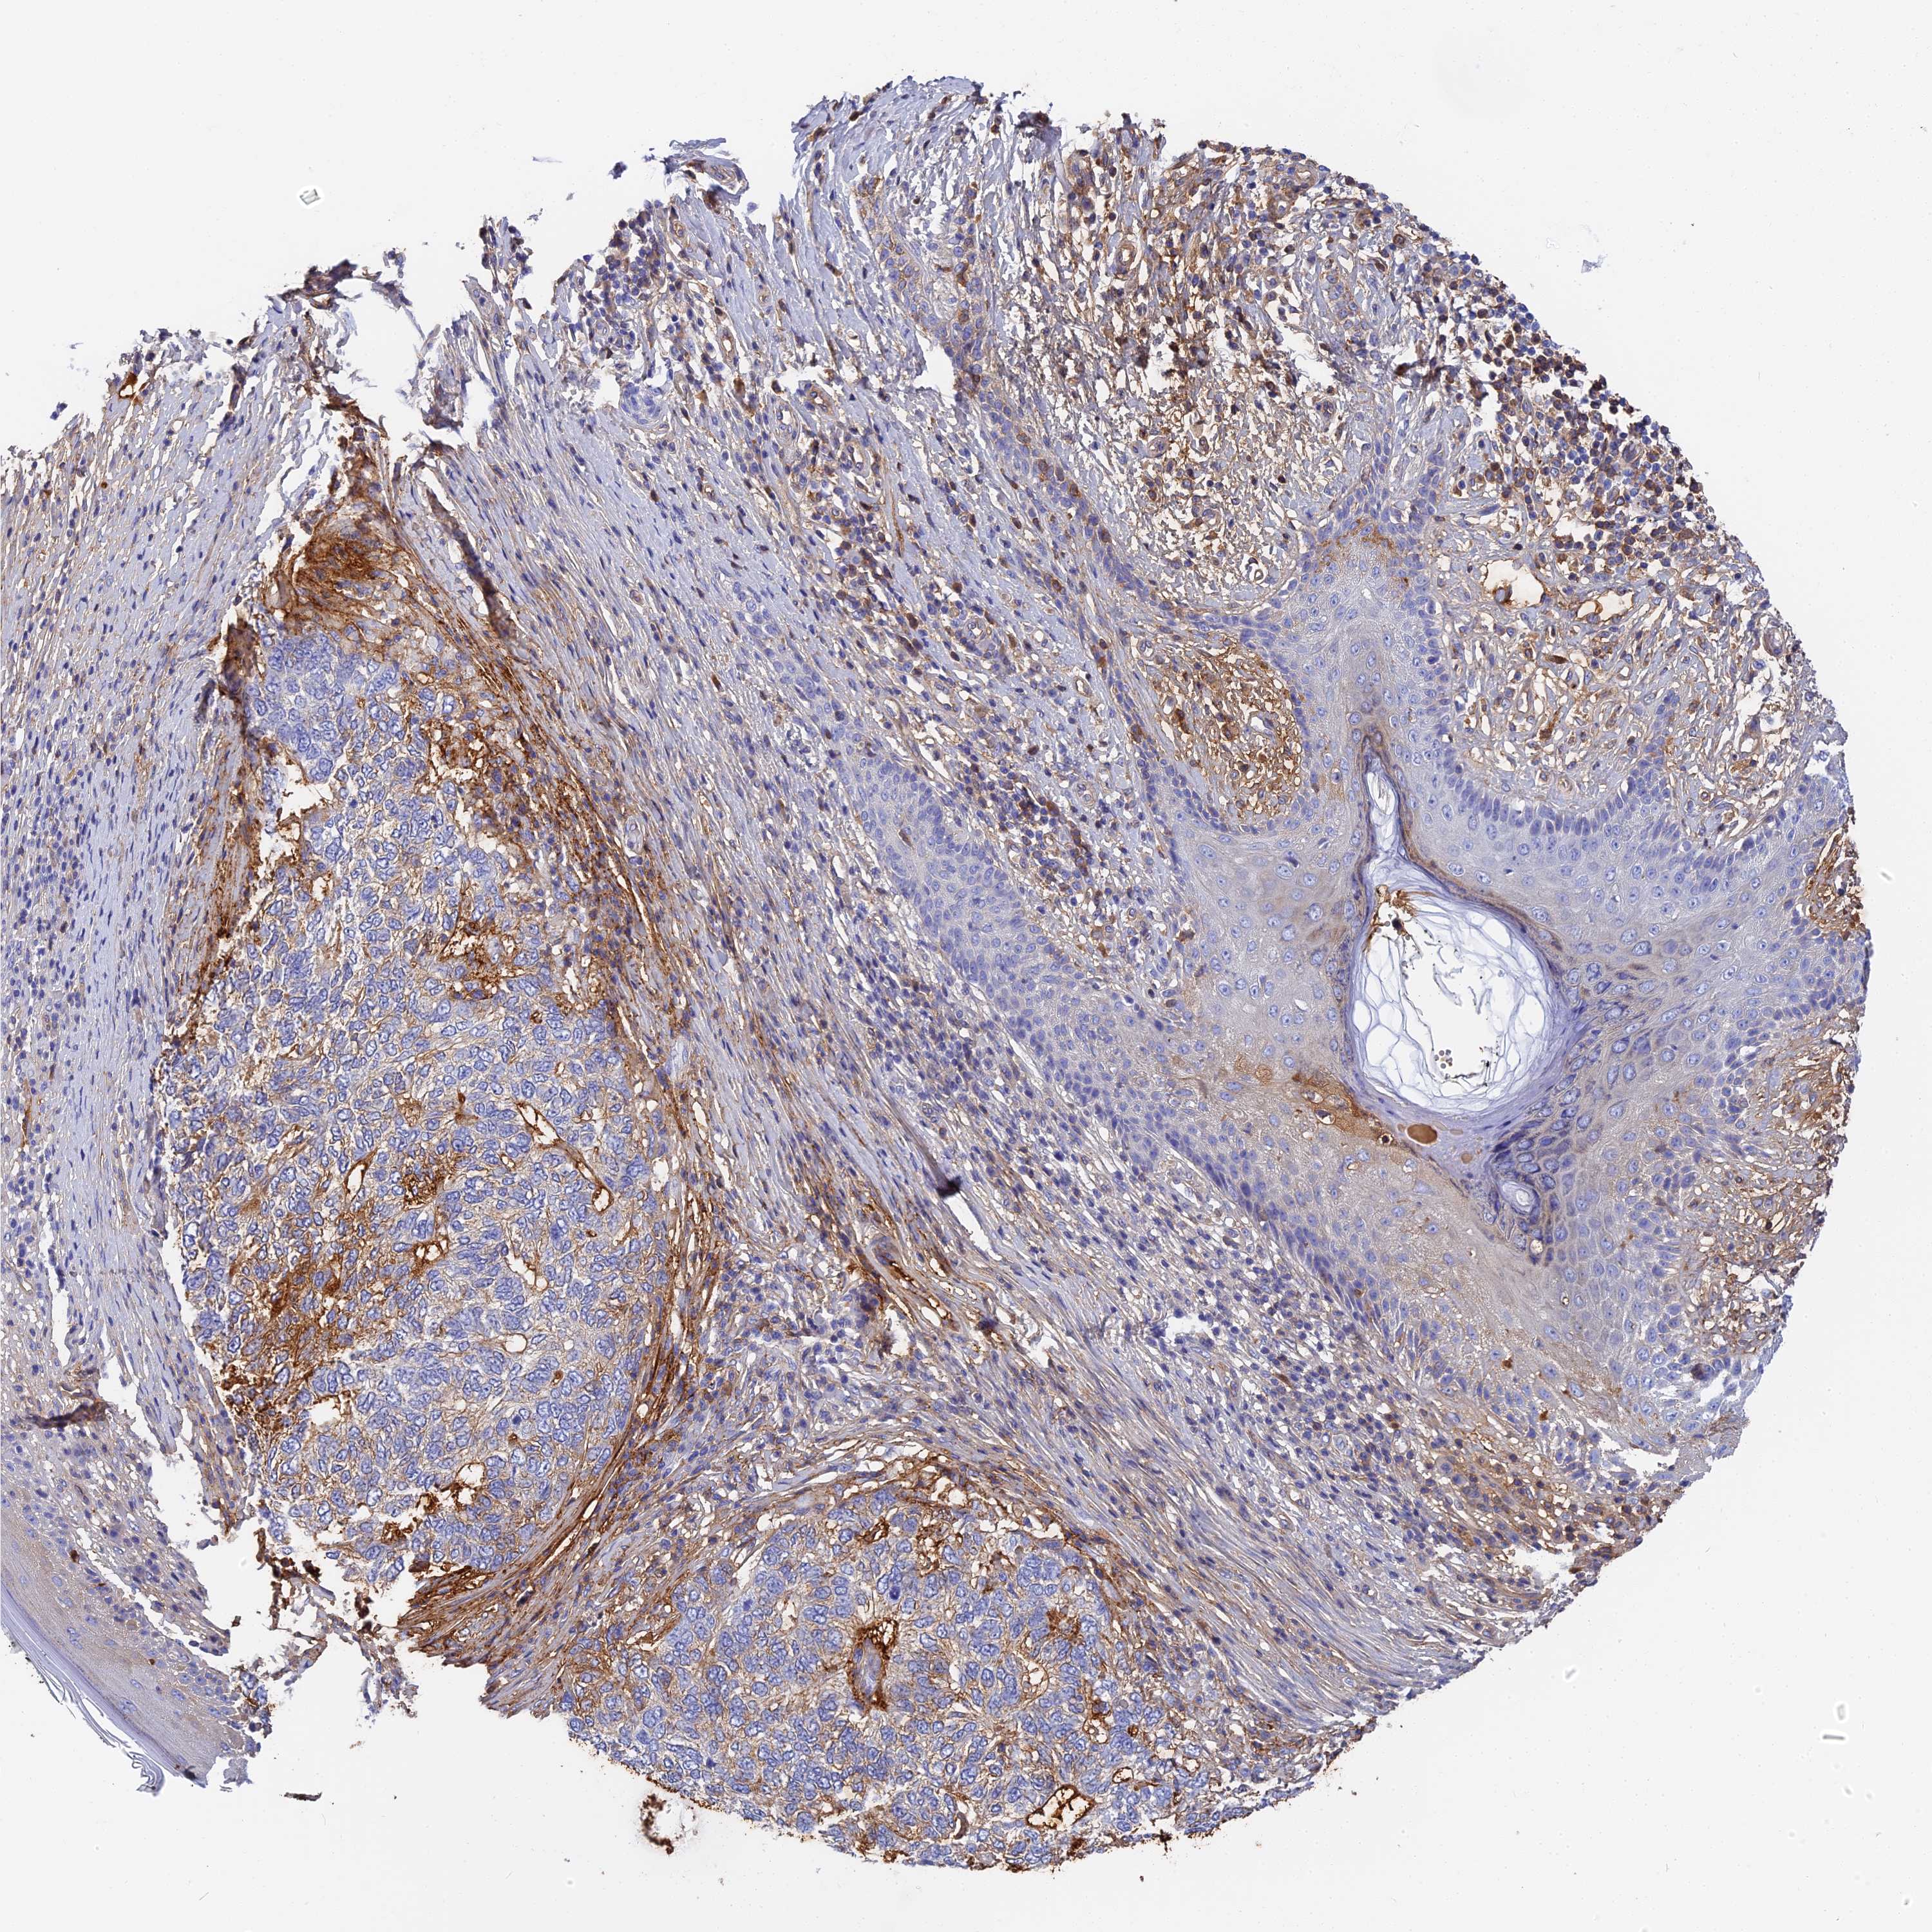

SKIN CANCER - Protein expressioni

A mouse-over function shows sample information and annotation data. Click on an image to view it in a full screen mode. Samples can be filtered based on level of antibody staining by selecting one or several of the following categories: high, medium, low and not detected. The assay and annotation is described here.

Antibody stainingi

Antibody staining in the annotated cell types in the current human tissue is reported as not detected, low, medium, or high, based on conventional immunohistochemistry profiling in selected tissues. This score is based on the combination of the staining intensity and fraction of stained cells.

Each image is clickable and will lead to virtual microscopy that enables deeper exploration of all samples and also displays staining intensity scores, fraction scores and subcellular localization as well as patient and tissue information for each sample.

Antibody HPA041639

Antibody HPA042049

Basal cell carcinoma